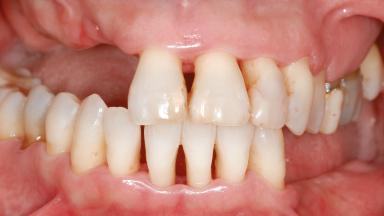

A 46-year-old woman was referred for treatment whose main complaints were mobility of her fixed partial dentures (right maxilla and left mandible) and periodontal bleeding during function. She also reported having taken systemic antibiotics to treat recurrent swelling in the area of the upper left molars. The patient had not seen a dentist for at least 2 years. She did not smoke and had no history of major systemic disease other than two minor orthopedic procedures some years back. The first-visit examination revealed poor plaque control, tooth mobility, periodontal disease, and a residual dentition widely associated with deep periodontal pockets.

Bone Volume Horizontally and vertically sufficient Horizontally deficient Deficient vertically or deficient vertically AND horizontally

Periodontal Status History of periodontitis or genetic predisposition